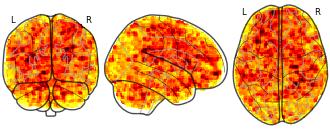

License information was derived automaticallyDescriptionBetween-group comparison of unmodulated brain activation before training (pre-training) in the DN condition. Shows baseline neural differences between TD and DLD groups prior to SL training.

This dataset includes whole-brain statistical maps from a longitudinal fMRI study investigating visual statistical learning (SL) in children aged 6–9 years with developmental language disorder (DLD; n = 27) and typically developing (TD; n = 35) peers. Participants completed an SL task involving visual sequences under two stimulus conditions: easy-to-name(EN; animal drawings) and difficult-to-name (DN; abstract Hebrew letters). Sequences were either structured (1-back transitional probabilities) or random. Functional scans were collected at two time points: before and after one week of home-based SL training.

At the first-level analysis, individual contrast maps were computed comparing BOLD responses to structured vs. random sequences (Statistic > Random), separately for each stimulus type. At the second level, full-factorial SPM12 models (2 Group × 2 Time) were implemented separately for EN and DN conditions. Crucially, group-level models included four z-scored covariates representing individual performance index (PI) for each group and session, enabling the analysis of brain–behavior associations and their modulation by group and training. Additional analyses included F-tests on PI covariates (Group × Time interaction) and t-tests comparing group differences in PI-related activation at each time point.

All functional images were acquired on a 3T Siemens Prisma scanner. Preprocessing included motion correction, normalization to MNI space, and spatial smoothing (6 mm FWHM). Data quality control included framewise displacement scrubbing and a minimum tSNR threshold of 100.